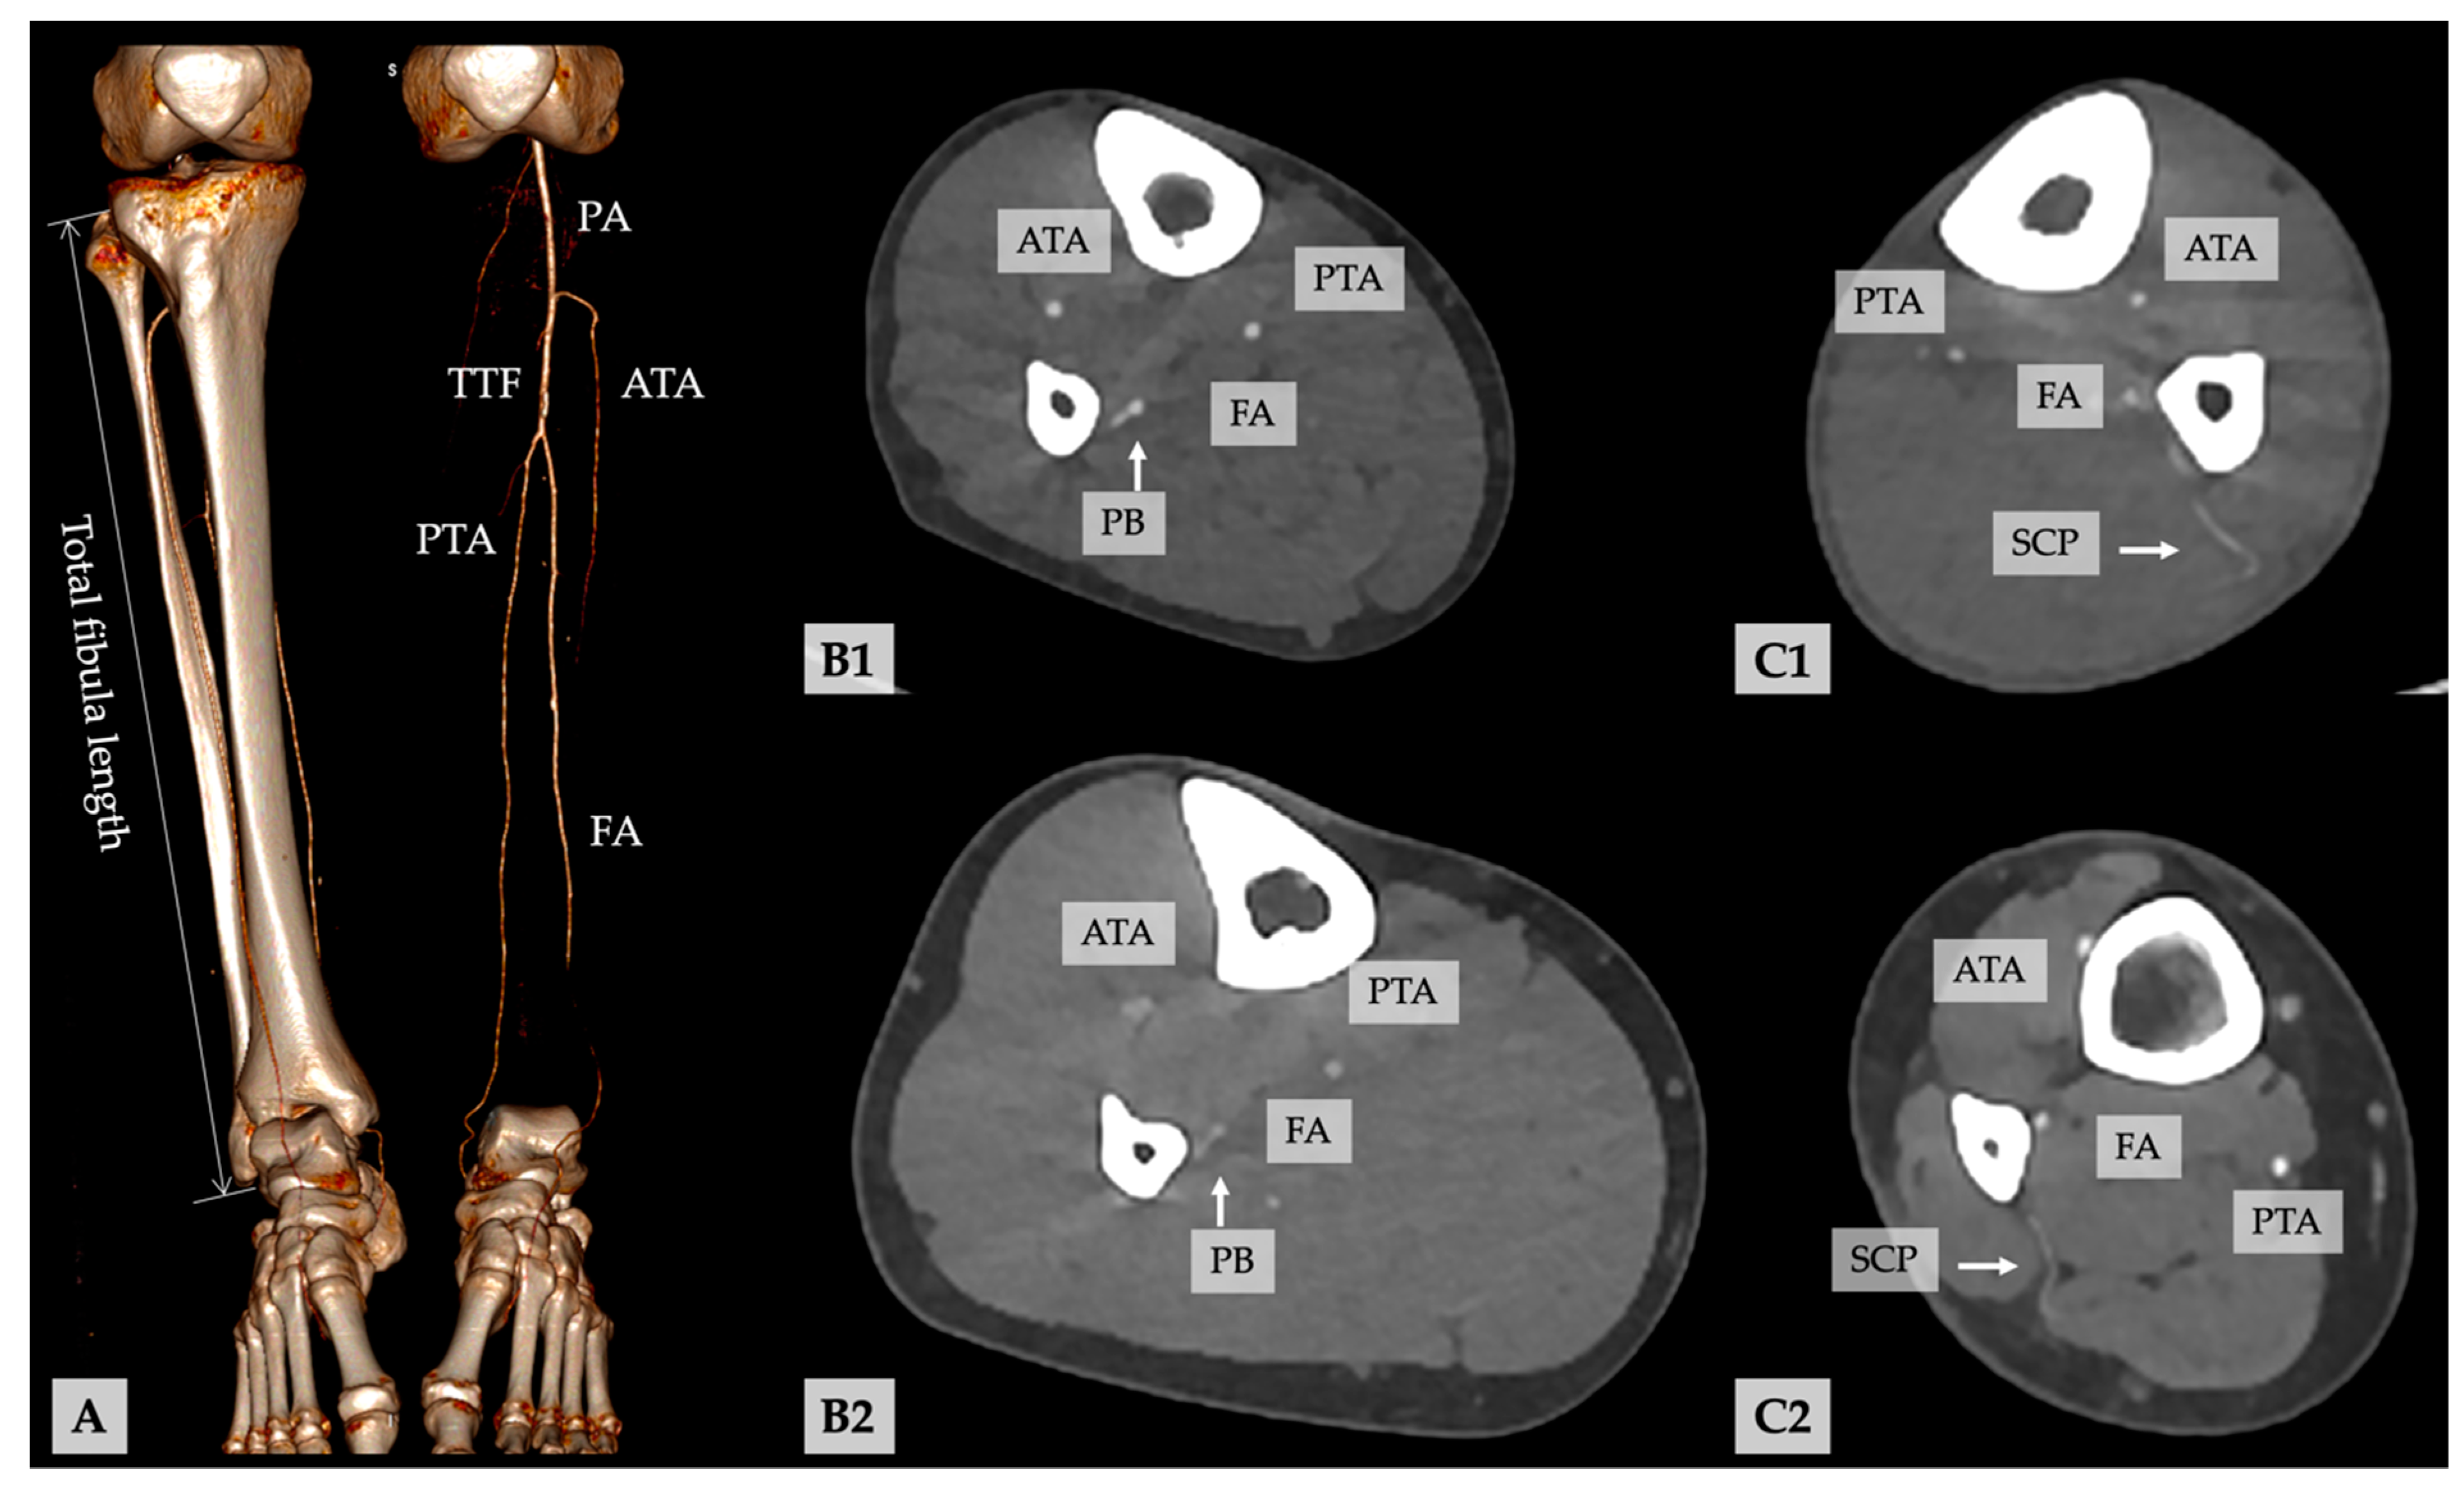

Figure 2.

(A) Volume rendering and virtual excision of the left tibia and fibula illustrate the vessel run-off along the lower leg. (B1,B2) Representative examples of periosteal branches (PB) and (C1,C2) septo-cutaneous perforators (SCP) of the FA in the axial CTA planes (ATA, anterior tibial artery; FA, fibular artery; PA, popliteal artery; PTA, posterior tibial artery; TTF, truncus tibiofibularis).

The localization of the main visible (musculo-)septo-cutaneous perforators and periosteal branches (PB) of the FA were identified in the axial plane on CTA (Figure 2), and the distance of the exit of the perforators of the FA to the distal tip of the fibula was recorded. The shortest distance between the surface of the fibular bone and the center of the FA and the diameter of the FA were recorded in 0.5 mm intervals and 50 mm above the distal tip of the fibula bone. The internal diameter of perforators was also recorded. In cases of doubt, impartial, experienced radiologists (C.A. and F.R.) were consulted.

Fibula length, bone and vascular anomalies, vascular anatomy and branching pattern of the calf [52], length of the TTF, the shortest distance between the surface of fibular bone and center of the fibular artery (FA) in the axial plane, the internal diameter of the FA, and the number and length of skin perforators and bone feeders from the distal tip of the fibular bone to branching and between the branches (Figure 2). All measurements were recorded in millimeters. Body weight and height were collected from the medical records.